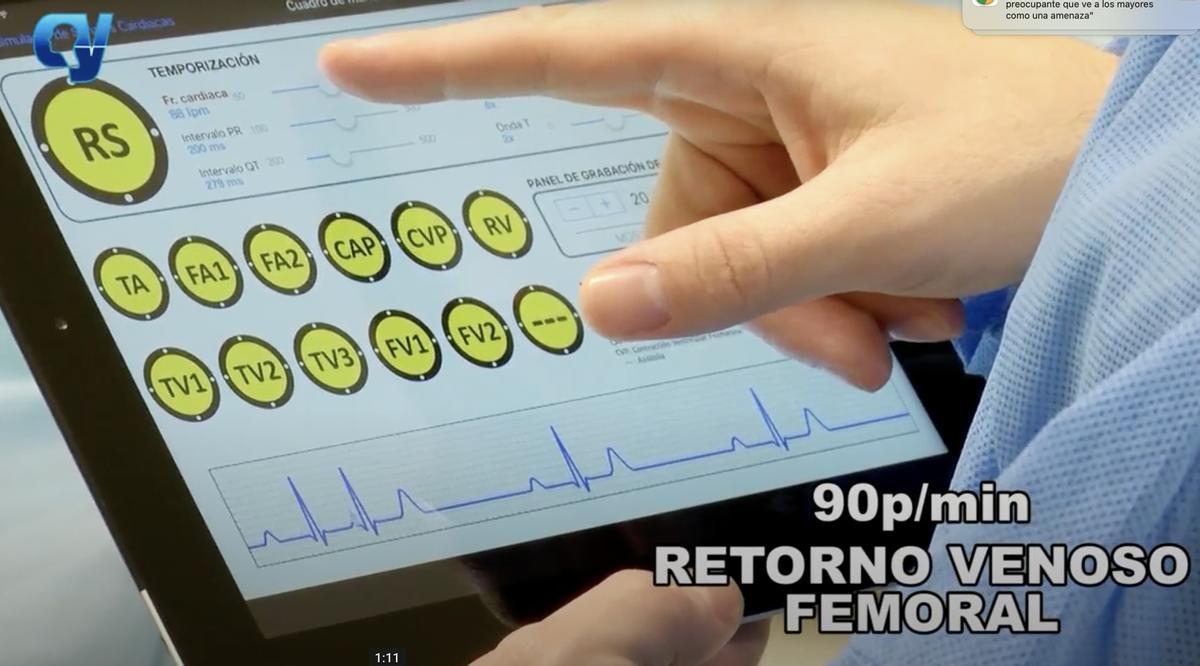

La Inteligencia Artificial también crea cyborgs, "hombres máquinas" para ayudar a los cirujanos en sus prácticas de aprendizaje con cadáveres donados a la ciencia en los que, mediante microchips que se introducen bajo la piel e impulsos eléctricos, se recrea el sistema respiratorio.

También el circulatorio gracias a unas bombas controladas por IA que simulan las diferentes tipologías de ritmos cardiacos e impulsan los que se denomina pseudosangre, que circula por el cuerpo cuando los cirujanos cortan con el bisturí.

Pseudosangre

Esa sangre artificial (colorante líquido) sale si se rompe un vaso y el cuerpo "recupera el pulso" en un simulador clínico cadavérico que está teniendo una gran acogida en la formación de cirujanos de toda España pues el modelo mantiene la flexibilidad de un ser vivo.

Sistemas que se utilizan en el proyecto Cyborg de Anatomía